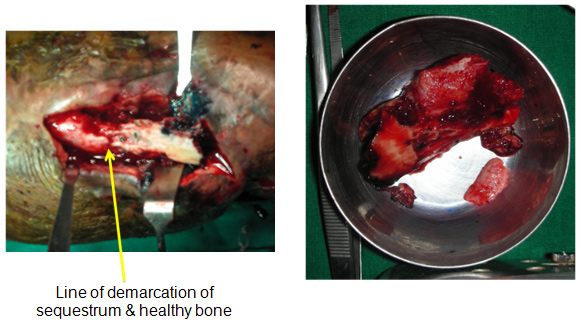

The only option really in my opinion was to do a proper debridement, clear the infection and then think of the reconstructive aspect.

In May 2011, we did the surgery for her and the plan was to do a thorough debridement, use local antibiotic in Calcium Sulphate pellets (Stimulan), and stabilise.

The debridement and the antibiotic pellets was the 'easy' part. How to stabilise a large defect (for I was pretty sure that was what we were going to have at the end of debridement.

|

| Central diaphysis of the Radius and Ulna sequestrated |